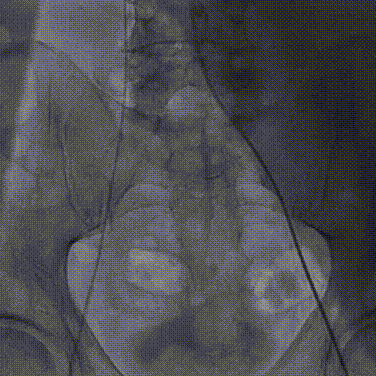

1.根据术前测量分析,采取右侧股动脉作为主入路,左股为辅入路,冠脉造影显示双侧冠脉灌注良好。

左冠造影

右冠造影

2.置入猪尾进行根部造影,造影可见主动脉根部大量钙化,瓣叶活动度低,冠脉灌注良好,中量反流。

根部造影